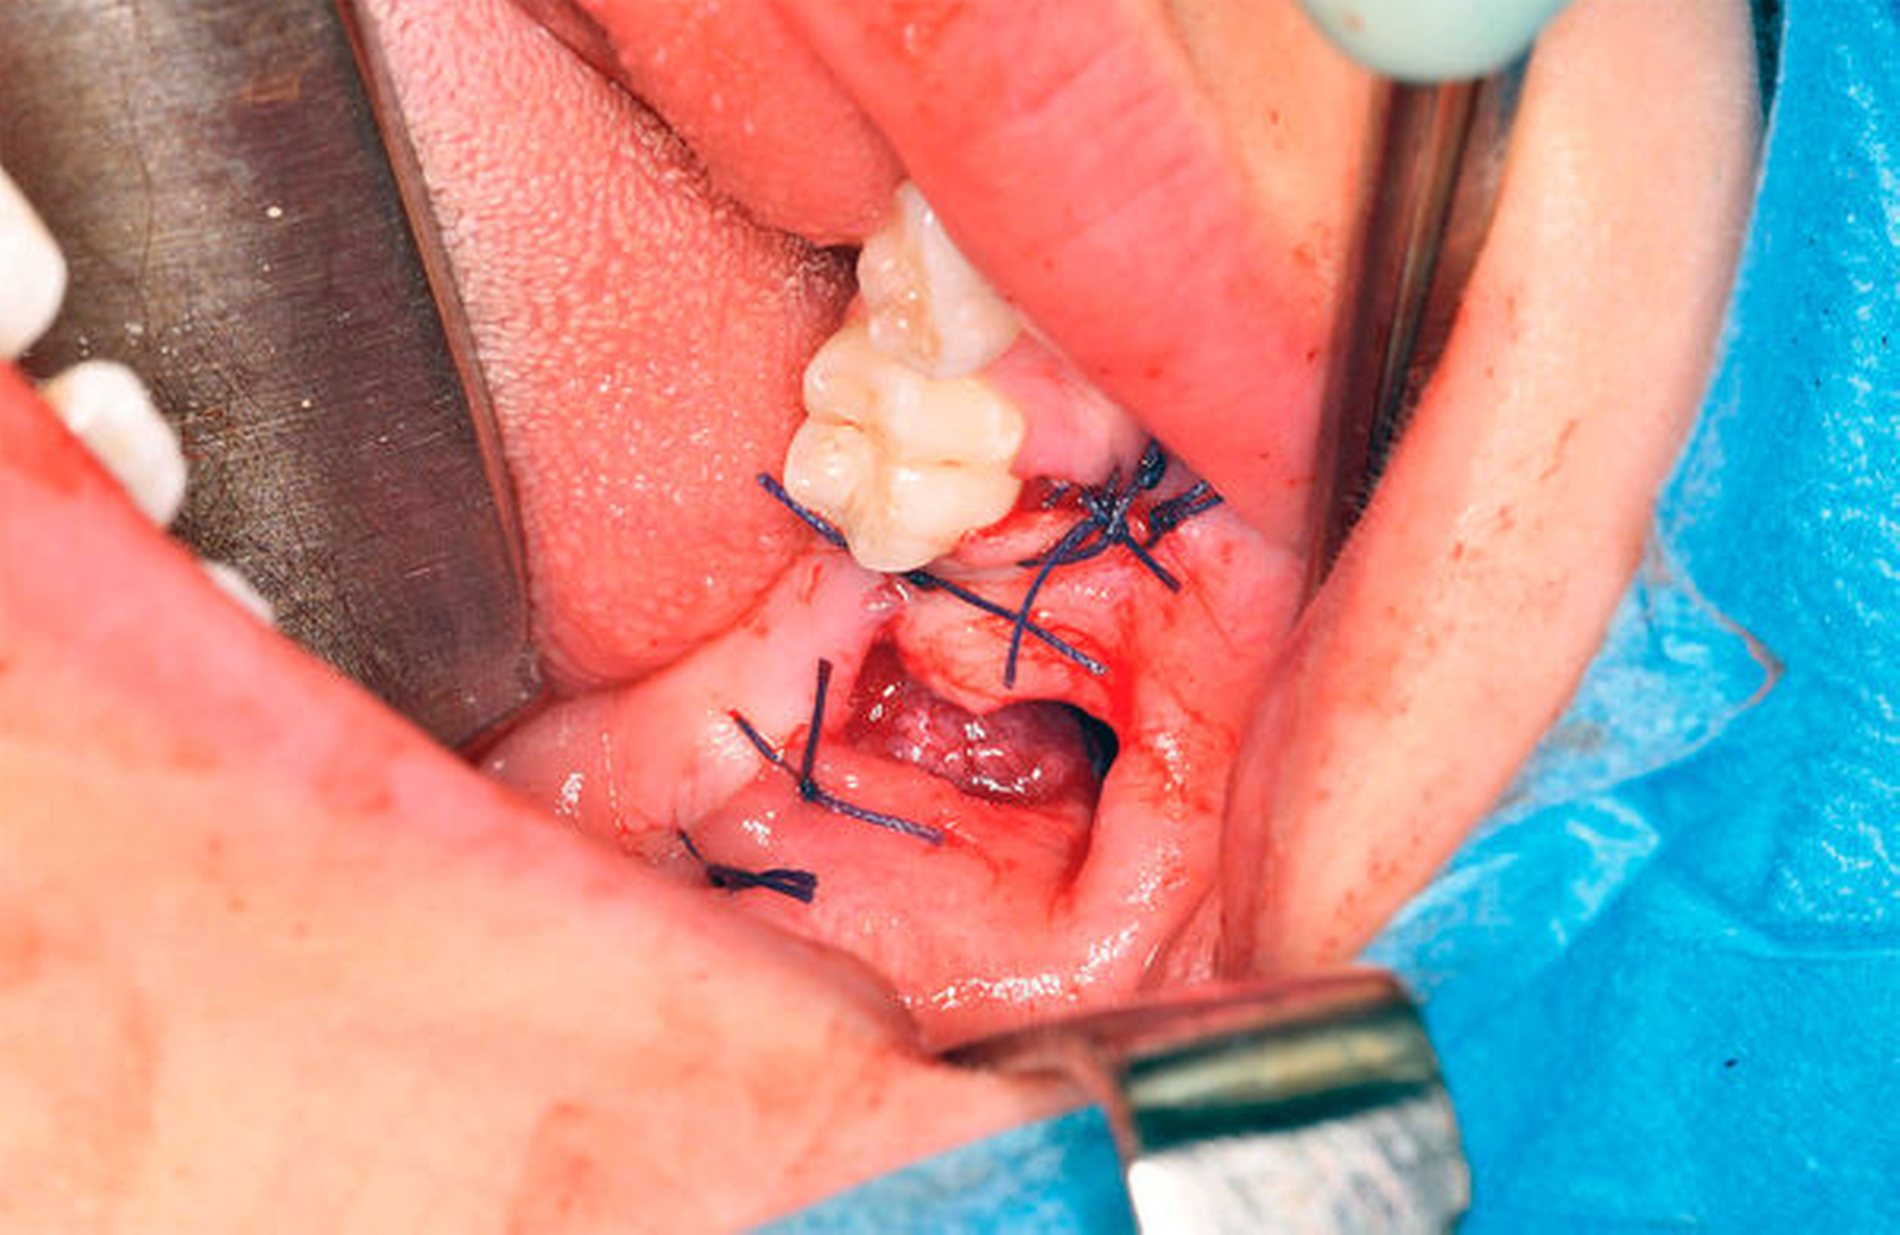

In Intubationsnarkose wurde vom aufsteigenden Ast kommend unter marginaler Schnittführung ein Mukoperiostlappen mit vestibulärer Entlastung am Zahn 45 präpariert. Unter vorsichtiger stumpfer Präparation erfolgte nun die Darstellung der Zyste (Abbildung 4) mit anschließender Eröffnung über einen osteoklastischen Zugang von vestibulär (Abbildung 5). Unter dem Schutz der Zähne 46 und 47 konnte der Zystenbalg mobilisiert und entfernt werden. Abschließend erfolgten der mehrschichtige Wundverschluss mit Fensterung nach vestibulär (Abbildung 6), eine intraoperative Alginatabformung zur Herstellung eines Obturators sowie die Einlage einer Tamponade.